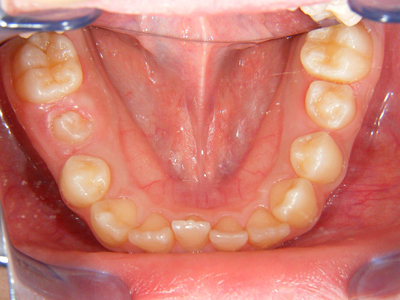

3. 術前下顎

下顎面観ではやはり右下1番の舌側転位、左下2,3番間の叢生が目立ちます。右下5番(第2小臼歯)が左側の同5番に遅れて萌出途中にあります。